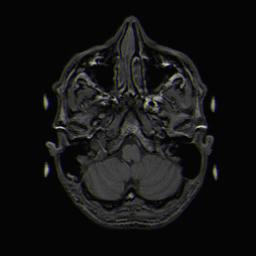

A T1-weighted magnetic resonance imaging (MRI) of a normal brain. White matter (light grey), grey matter (dark grey) and CSF (black) can be clearly identified.

Image credit to Dr. Laurent Hermoye. This image is licensed under the Creative Commons Attribution-Share Alike 3.0 Unported license.